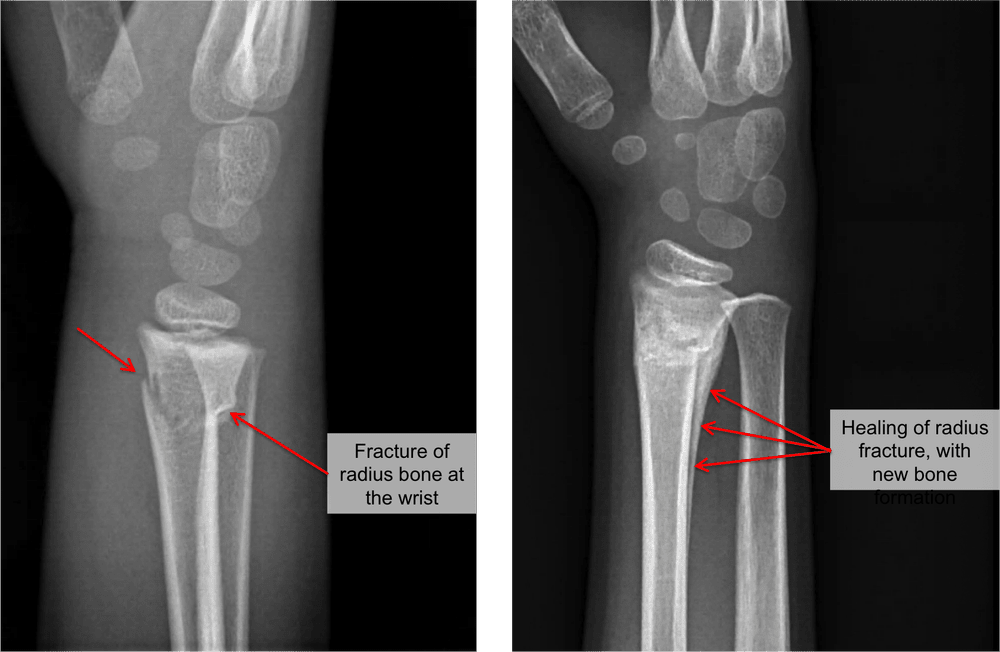

Buckle Fracture Wrist Nhs - Https Www Cambridgeshireandpeterboroughccg Nhs Uk Easysiteweb Gatewaylink Aspx Alid 17372 : Now that you have had your cast removed it is very important that you use your wrist as normally. Buckle fractures (also known as torus fractures) are very common injuries in children. A sling may help reduce discomfort. The bone buckles on one side rather than actually breaks and is commonly seen in children as their bones are soft and flexible. It usually takes four to six weeks for new bone to form to heal your fracture. Young bone is still soft and very flexible.

Children's bones are soft and very flexible. This injury is treated like a sprain and will not cause any long term problems. It can take longer if your arm or wrist was severely damaged. It usually takes four to six weeks for new bone to form to heal your fracture. A plaster cast usually prevents a fracture from moving, but allows your fingers to move.

The skin under the cast may be itchy for a few days but this should pass. Your child has broken their wrist. In most cases it takes around 6 to 8 weeks to recover from a broken arm or wrist. It is a stable fracture,. It can take longer if your arm or wrist was severely damaged. This is a common injury in children and normally heals very well in approximately three weeks with the use of a splint with no need for a larger plaster. The other side of the bone remains intact. Buckle fracture of the radius (forearm bone) this leaflet aims to answer some of the questions that you or your child may have about managing a buckle fracture, including removal of the splint at home. It is a minor fracture which heals with minimal intervention. This injury is treated like a sprain and will not cause any long term problems. A buckle fracture occurs when one side of the bone bends or is compressed but does not suffer a break. It usually takes four to six weeks for new bone to form to heal your fracture. Incomplete compression fracture at the metaphysis of the distal radius, ulna or both in which one cortex is disrupted, and the other remains intact.